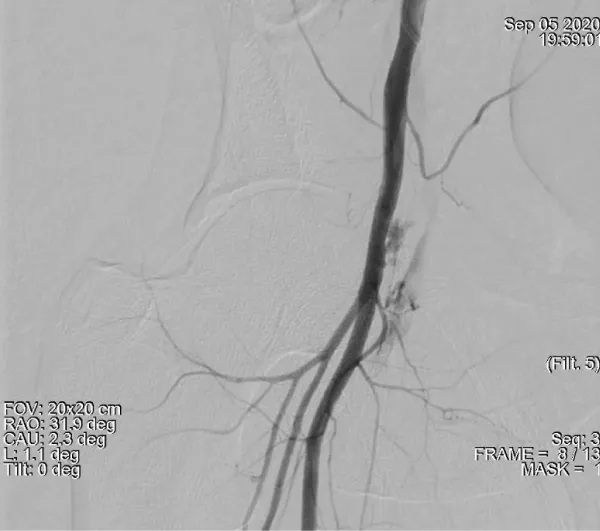

Download Image

Figure 2: Demonstrates a large amount of extravascular contrast with the right iliac angiogram location near the middle third of the femoral head. suggestive of active bleeding from mid right common femoral artery into the pelvis.

The case presented here can be considered as a case of RPH resulting from normal lower site puncture of common femoral artery as contrast leakage on angiography is at the level of the middle 1/3 of the femoral head only (Figure 5). Here RPH can be due to multiple puncture (two leakage points can be seen on angiography) and can be explained by direct superior connection of the anatomical femoral sheath with the retroperitoneum leading to RPH [3]. The other risk factor could be a low BSA which was 1.61 meter².